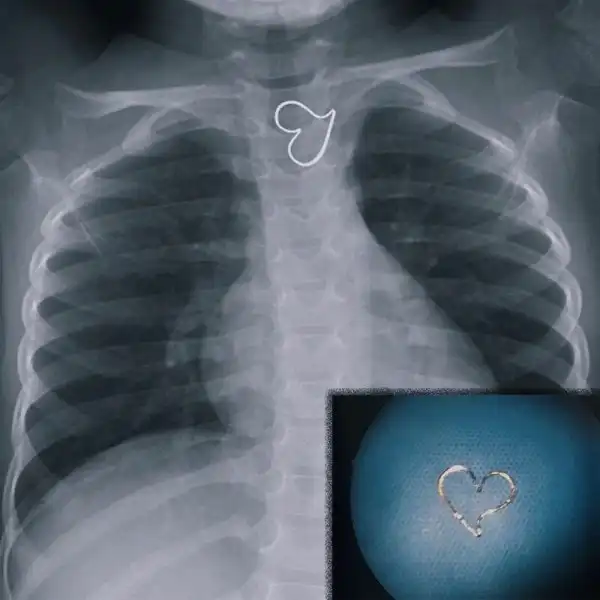

Когда забыл снять пирсинг и украшения

Проглотила кулон